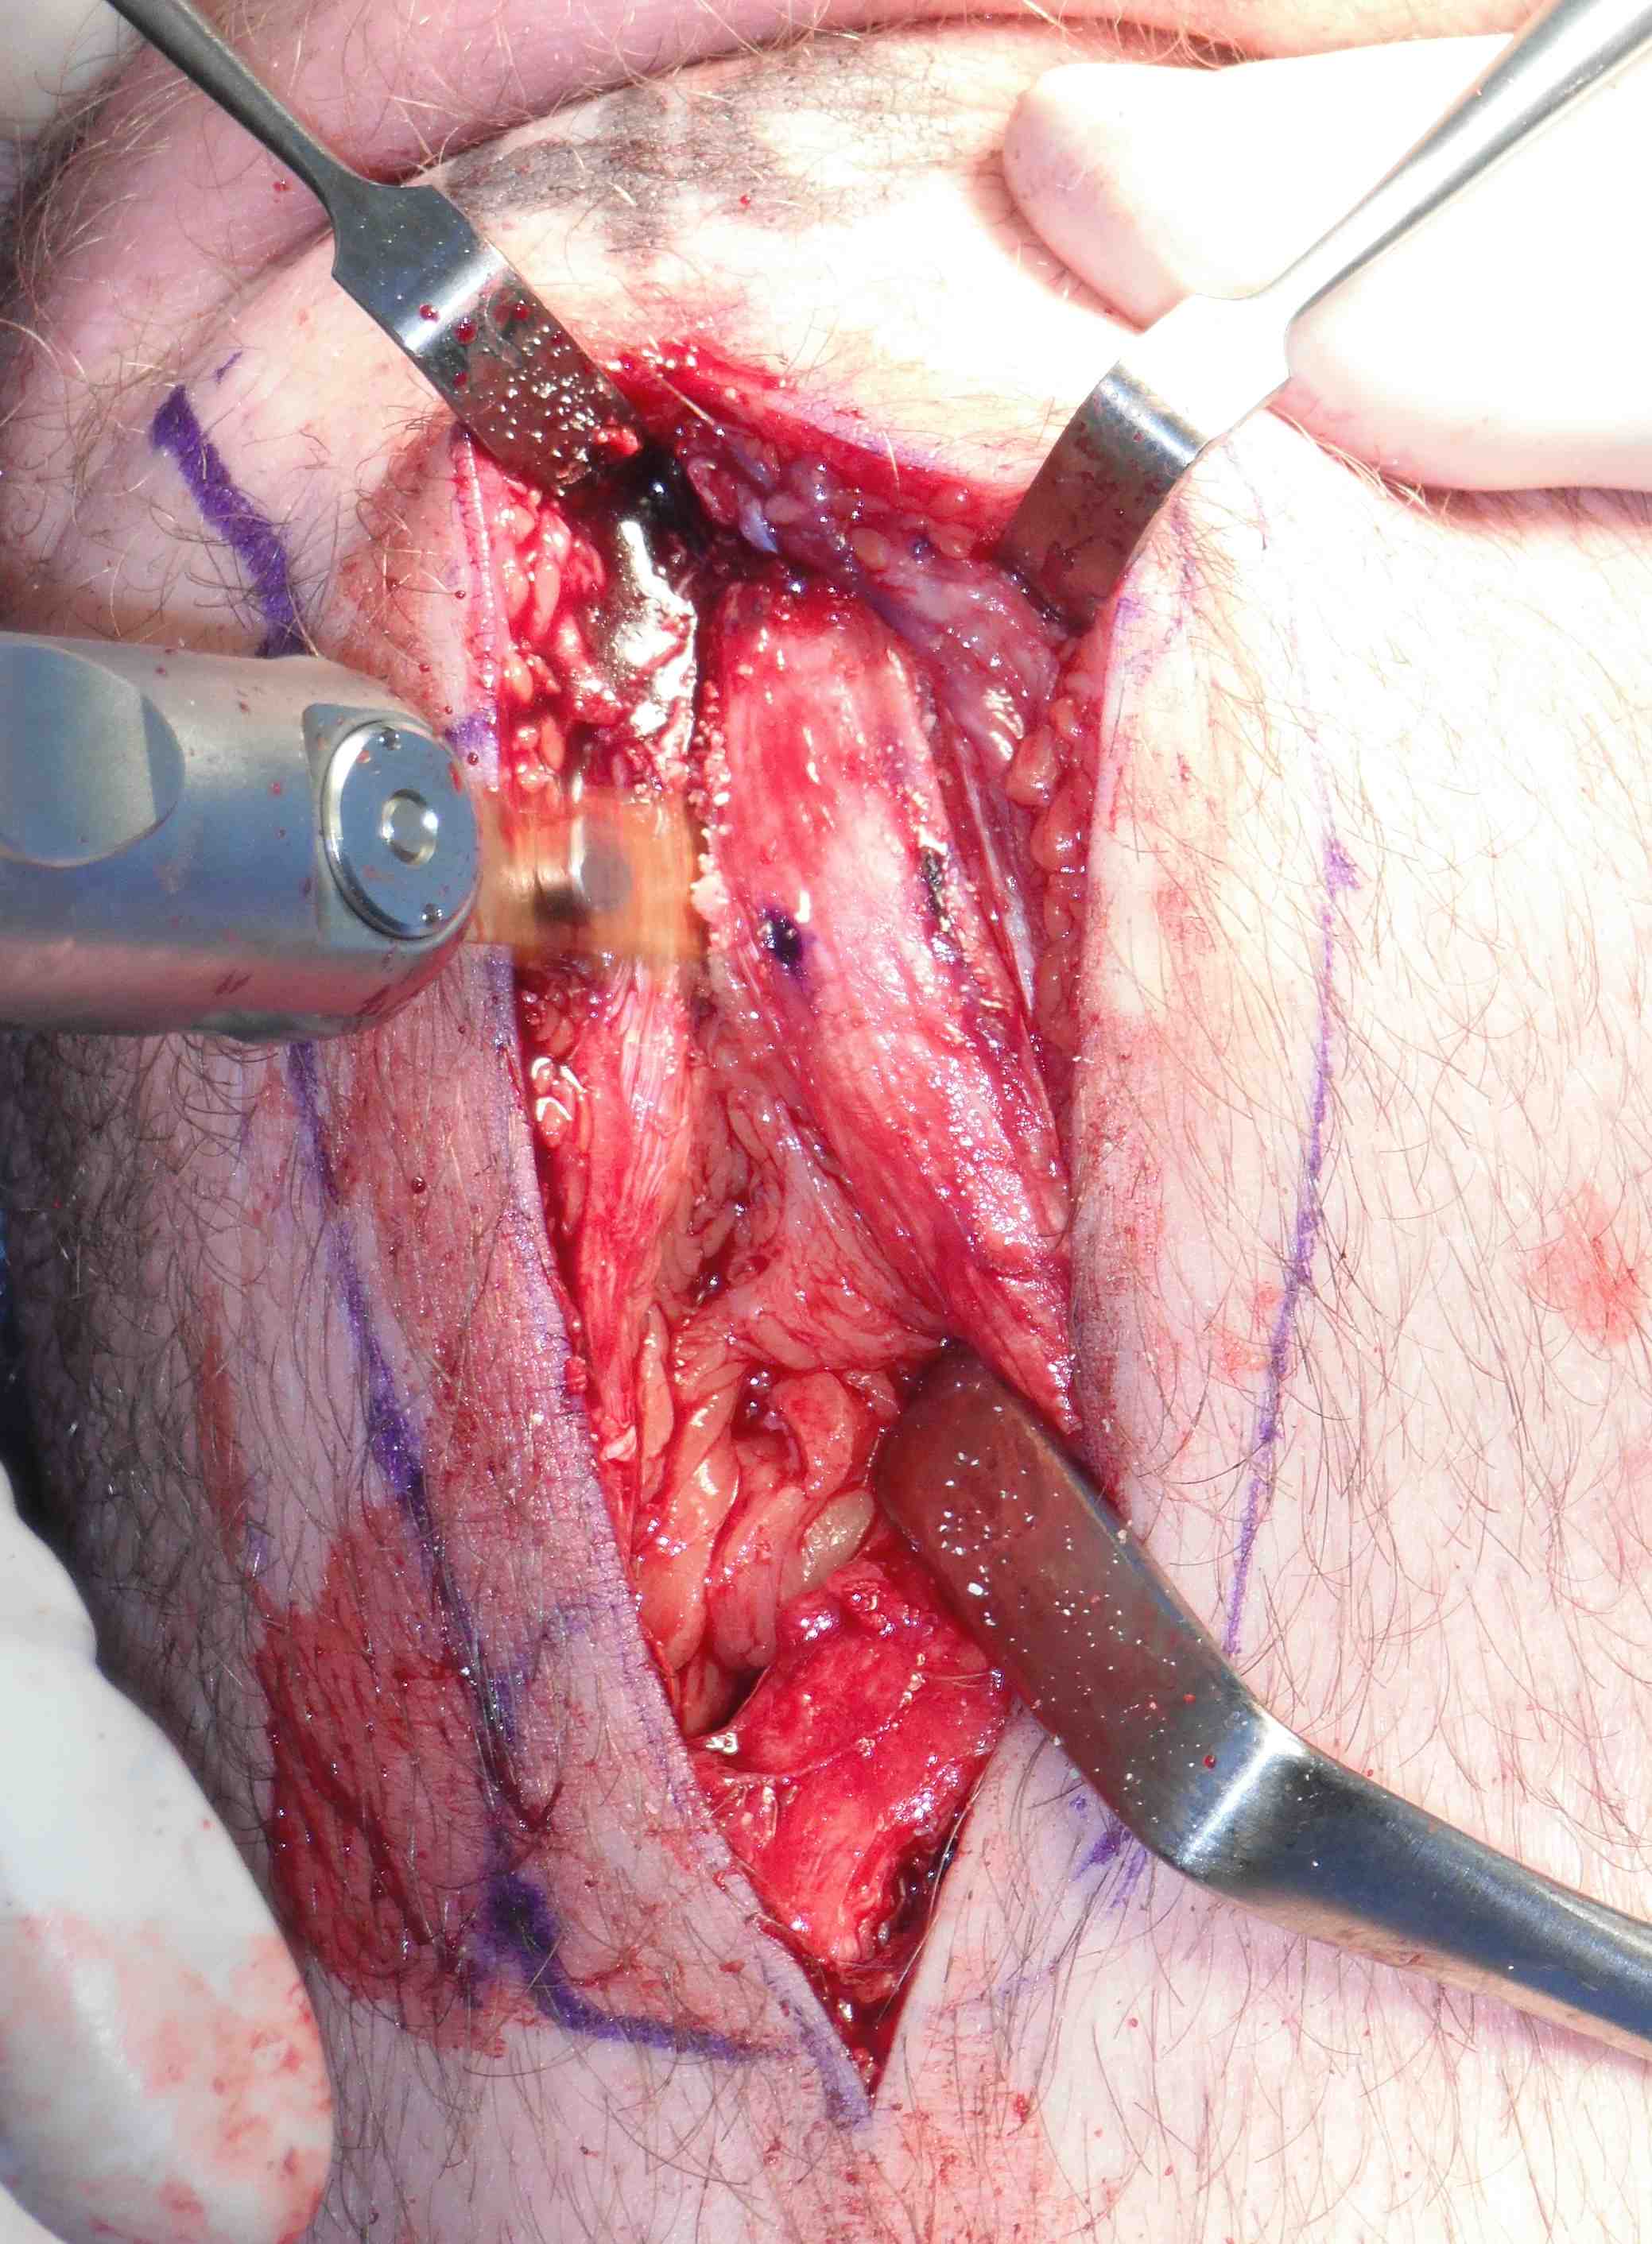

Midline incision over patella tendon

- from lower pole of patella to tibial tuberosity

- dissect fascia off tendon carefully without injuring tendon

- identify medial and lateral margins and assess tendon width

Use marking pen to mark central 1 cm of tendon at distal pole patella

- can increase this to 12 - 14 mm in large male if sufficient tendon width

- use knife to cut from 2 cm on patella down medial side

- ensure leave 5 mm tendon medially

- extend 2cm down tibial tuberosity

- remeasure and cut laterally